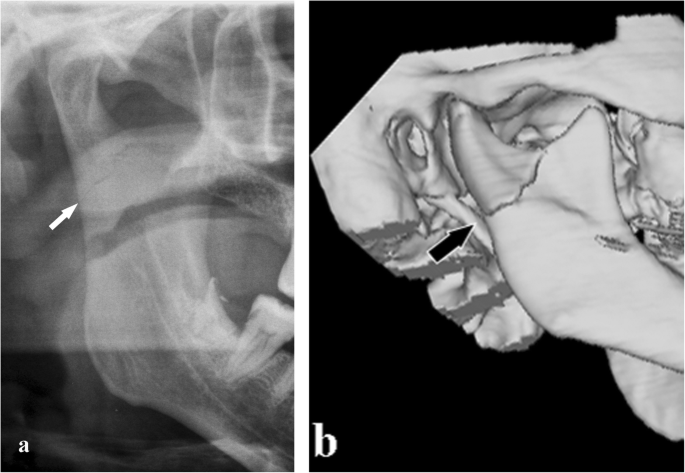

The condylar neck is the weakest area of the mandible. It responds to the need to defend the middle cranial fossa from the traumatic energy that would be transmitted to it by the mandibular condyle. The interruption of the traumatic energy at the site of the condylar neck is a means of defence for the endocranium. In fact, only few cases of glenoid fossa fractures and endocranial dislocation of mandibular condyles have been described [28] (Fig. 19). Moreover, the fracture of both condylar necks is common when the trauma is applied to the chin symphysis.

Fracture of the glenoid fossa of the temporal bone. a Cropped panoramic radiograph shows a reduction of the articular space. The condylar head seems to be higher than its usual location (arrow). b, c Computed tomography coronal and sagittal sections. A slight upward movement of the mandibular condyle associated with a glenoid fossa fracture of the temporal bone is observed (arrows)